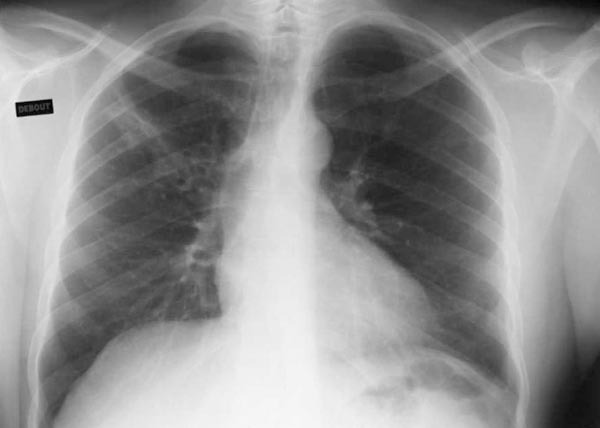

Tuberculose pulmonaire

Radiographie thoracique. Infiltrat du sommet droit.